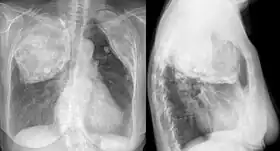

![]() X-ray in an elderly woman after pneumonolysis | |

The technique involved surgically creating a cavity underneath the ribs in the upper part of the chest wall and filling this space with some inert material. A variety of substances were typically used and included air, olive or mineral oil, gauze, paraffin wax, rubber sheeting or bags and Lucite balls. The inserted material would force the upper lobe of the lung to collapse.